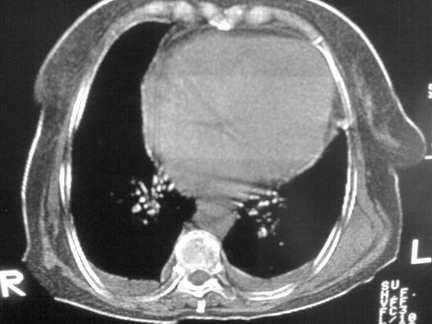

标题: CT13142:女 80 胸闷、气短、1w [打印本页]

标题: CT13142:女 80 胸闷、气短、1w

缩窄性心包炎

左室为主的心脏增大。

右肺感染;双侧胸腔少量积液,心影增大,可能与心功不全有关;胸内甲状腺肿。

右肺炎性变,双侧甲状腺肿,胸膜肥厚,心影增大考虑心功能不全.

胸内甲状腺肿;右肺中叶感染;双侧胸腔少量积液;心影增大,考虑有心功能不全。